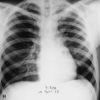

ÃÙ»ÀÒ¾·Õèà¡ÕèÂÇ¢éͧ